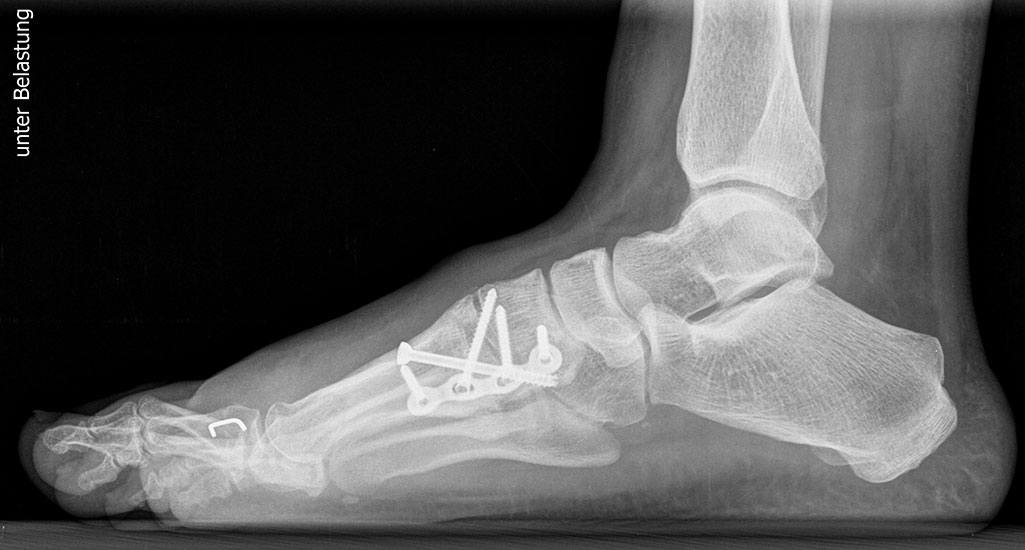

Röntgen

Standard ist die belastete Röntgenaufnahme des Fußes dorso-plantar und seitlich. Günstig ist eine Röhrenkippung von 10°-20°, um die Gelenke der Lisfranc-Linie einsehen zu können.

Ergänzend kann eine Schrägaufnahme hilfreich sein. Bei Metatarsalgien oder Pathologien der Sesambeine liefert die Sprinteraufnahme zusätzliche Informationen. Bei einer Pes planovalgus Fehlstellung wird ergänzend ein Saltzman view durchgeführt.

Bezüglich der Operationstechniken wird von früher häufig durchgeführten alleinigen Weich­teileingriffen am Großzehengrundgelenk aufgrund hoher Rezidivraten abgeraten 15. Die Operation nach Mc Bride mit lateralem Release, Exzision des lateralen Sesambeins, Abtragen der Pseudoexostose, Sehnenetransfer des M. adductor hallucis und mediale Kapselraffung zeigte unbefriedigende Mittel- und Langzeitergebnisse 16. Die Cerclage fibreux (mediale Kapselraffung) und das laterale Kapselrelease wird heute in Kombination mit einem knöchernen Eingriff angewendet. Bezüglich des Einsatzes von minimalinvasiven Operations­techniken vor Wachstumsabschluss liegen bisher keine Daten vor. Alle Osteotomien lassen sich nach Bedarf miteinander kombinieren. Es ist darauf zu achten, dass Osteotomien keine offenen Wachstumsfugen verletzen.

• medial aufklappende Cuneiforme I Osteotomie 1522

• Nach Schluss der Wachstumsfugen: TMT I Arthrodese nach Lapidus 2425